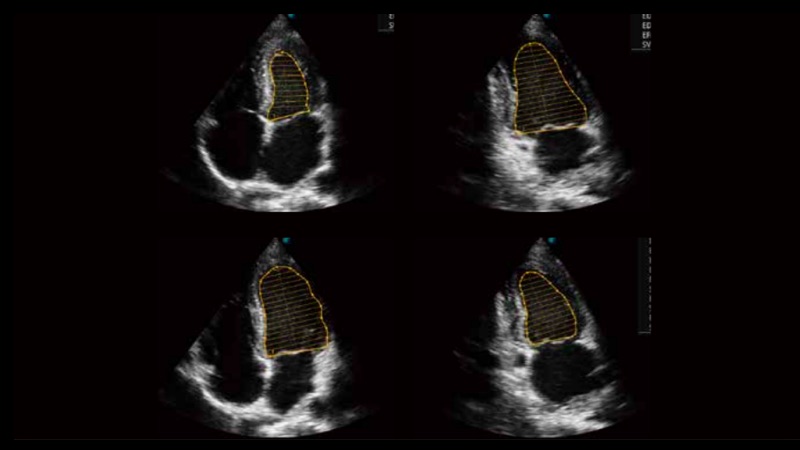

自動識別收縮和舒張末期心肌內(nèi)膜,自動計算射血分?jǐn)?shù)EF值。